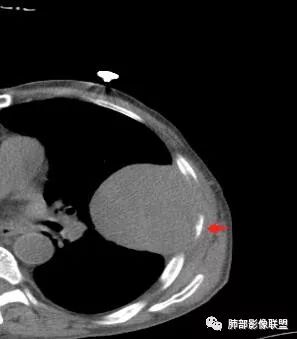

• 胸CT:左肺上叶实性占位,病灶与支气管无关,病灶对斜裂挤压,病灶周围光滑,未见分叶、毛刺;纵隔窗可见病灶内低密度区,病灶对胸壁侵袭,并可见肋骨破坏。

左肺上叶软组织肿块,叶间裂膨隆,肿块部分边缘光滑,密度不均,可见坏死,临近肋骨吸收破坏,与支气管关系不密切,增强后不均匀强化,考虑恶性肿瘤,肉瘤样癌可能大

胸CT:左上肺实性大肿块,边缘光滑,突破胸膜侵犯肋骨及肋间肌,纵隔淋巴结肿大,增强呈轻度强化,可见明显片状坏死。

老年男性,左肺上叶舌段胸膜下肿块,外朝内生长,对应支气管受压变窄,肿块边界清晰,邻近胸膜胸壁和肋骨受侵犯,增强扫描明显不均匀强化,内有较多坏死,考虑恶性,首先肉瘤样癌,鉴别低分化腺癌。

鳞癌因为侵袭性力较强,容易直接侵犯胸膜、胸壁,而周围型肺癌侵犯胸壁的90%癌肿是鳞癌,这也是鳞癌的一个特征性表现。邻近胸壁的脂肪层消失,胸壁肿块形成或有肋骨皮髓质边界不清的侵蚀破坏(而非边缘硬化或崩解)是瘤体向周围直接侵犯的可靠征象。